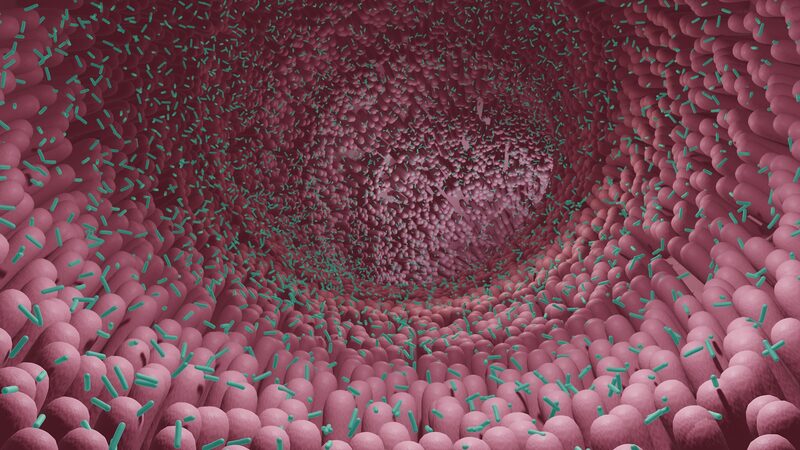

¿Sabías que la clave para envejecer con gracia podría estar en tu intestino? 🧐 Investigaciones recientes de científicos chinos sugieren que nuestro microbioma intestinal—sí, esas diminutas bacterias en nuestro sistema digestivo—podrían jugar un papel significativo en cómo envejecemos. 🚀

Pero aquí es donde se pone interesante: los investigadores encontraron que la composición de los microbios intestinales está asociada tanto con la salud metabólica como con la edad. En personas mayores de 60 años, aquellas con un microbioma intestinal \"más joven\" parecían tener un riesgo reducido de enfermedades cardiovasculares, incluso si eran metabólicamente poco saludables. 🤯

Esto significa que mantener nuestro microbioma intestinal juvenil podría ser un cambio trascendental para promover la salud del corazón y la longevidad. 🏃♀️🌟 Así que la próxima vez que pienses en tu salud, no olvides a tus compañeros microbianos—¡podrían ayudarte a mantenerte joven de corazón! 😉

El estudio sugiere que la edad microbiana intestinal podría ser un biomarcador prometedor para predecir el riesgo de enfermedades cardiovasculares. ¿Quién diría que microbios tan pequeños podrían tener un impacto tan grande en nuestras vidas? 🌟